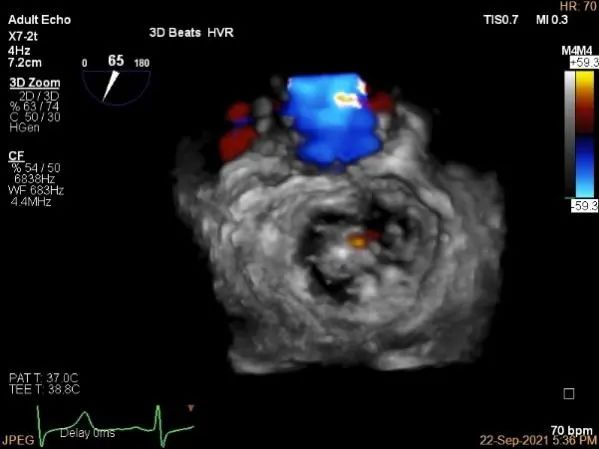

3D:P1区脱垂并腱索断裂,部分AC受累,Width:11.4mm

3D-color:重度MR,4级

3d-color确认残余分流情况